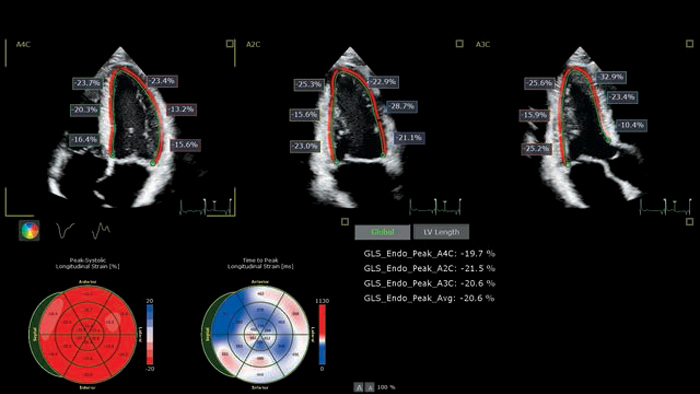

Using advanced ultrasound tools to assess CTRCD

Time-consuming methods are overcome by applying Philips Anatomically Intelligent Ultrasound (AIUS) to cardiotoxicity prevention.